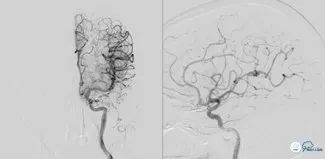

对左侧大脑后动脉取栓后后复查造影提示:左侧大脑后动脉恢复前向血流mTICI3级;右侧大脑后动脉P1远端未见显影。与左侧进行相同操作;synchro导丝引导select plus 微导管通过血栓段至右侧大脑后动脉P2段,微导管造影确认真腔后,跨越闭塞段释放solitareAB 6-30取栓支架,等待5分钟,中间导管在支架锚定下引导至基底动脉尖端部,保持负压抽吸,先超选到右侧大脑后动脉P1段进行取栓。

图7

取栓后复查造影提示:基底动脉级双侧大脑后动脉前向血流mTICI 3级,血管腔内未见血栓级狭窄影像,左侧椎动脉通道未见明显痉挛、夹层等影像。

图8